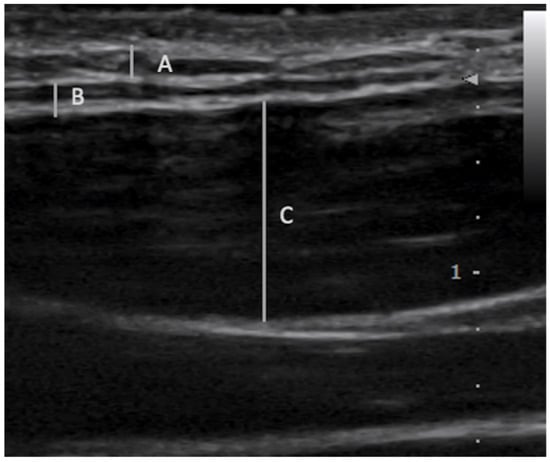

2.1. Fascial Layer Specific Hydromanipulation (FLuSH)